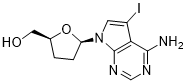

馬鞍山致研生物醫(yī)藥科技有限公司成立于馬鞍山市鄭浦港新區(qū)現(xiàn)代產(chǎn)業(yè)園。公司專(zhuān)注于生物小分子、醫(yī)藥中間體相關(guān)產(chǎn)品的研發(fā)和生產(chǎn),產(chǎn)品主要包括DNA亞磷酰胺單體、RNA亞磷酰胺單體、特殊單體以及按照客戶(hù)要求定制的RNA和DNA,并且公司提供定制合成等方面的研究服...

馬鞍山致研生物醫(yī)藥科技有限公司成立于馬鞍山市鄭浦港新區(qū)現(xiàn)代產(chǎn)業(yè)園。公司專(zhuān)注于生物小分子、醫(yī)藥中間體相關(guān)產(chǎn)品的研發(fā)和生產(chǎn),產(chǎn)品主要包括DNA亞磷酰胺單體、RNA亞磷酰胺單體、特殊單體以及按照客戶(hù)要求定制的RNA和DNA,并且公司提供定制合成等方面的研究服...